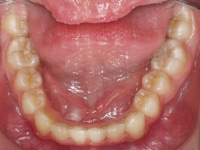

El paciente A.J. de 11 años, acude a nuestra consulta con apiñamiento maxilar importante. El canino lateral (12) está en mordida cruzada. Presenta una Clase II molar y canina, y la línea media está desviada. Se realizó un tratamiento con brackets autoligables metálicos de smartclip 022. La duración del tratamiento fue de 22 meses.

El paciente actualmente ha terminado el tratamiento con brackets y lleva una contención fija de 2-2 en maxilar y 3-3 en mandibular; para complementar también lleva una férula ESSIX durante la noche.

INICIO FINAL